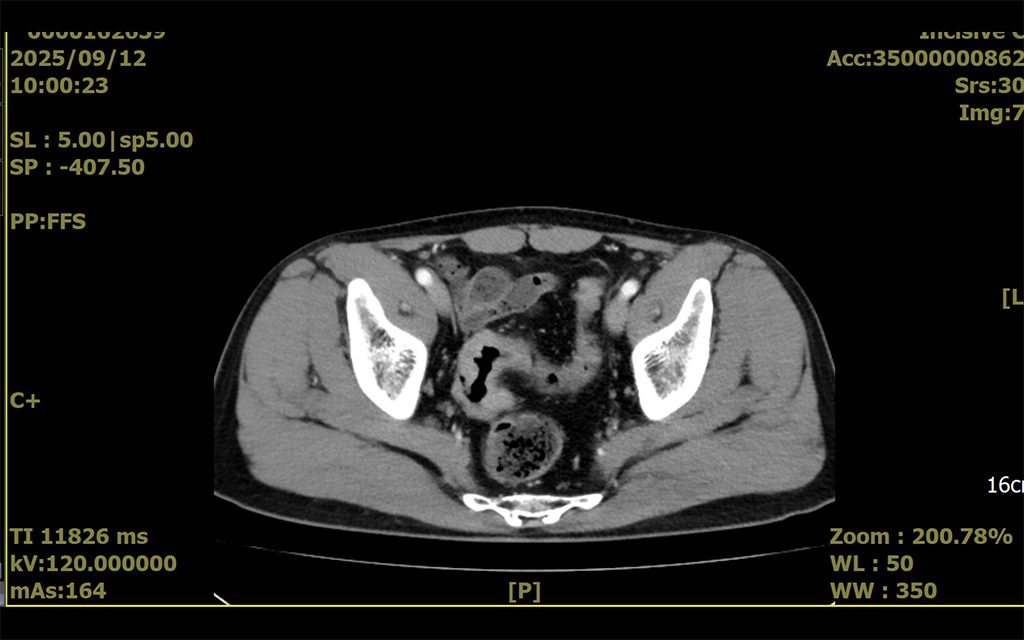

50歲男性因健康檢查發現糞便潛血反應呈現陽性,進一步至衛福部臺南醫院接受大腸鏡檢查而發現大腸癌,隨即在院接受手術治療,由外科主任許凱熙醫師為其進行Hugo機器人輔助微創手術,術後恢復迅速良好,很快即重回工作崗位及正常生活。

衛生福利部臺南醫院外科主任許凱熙表示,大腸直腸癌是國內最常見的癌症之一,定期接受糞便潛血反應篩檢,可及早發現大腸直腸癌加以及時治療。大腸直腸癌的治療以手術為主,由最早期傳統剖腹手術,到腹腔鏡微創手術,再演進到最先進的機器人輔助微創手術。